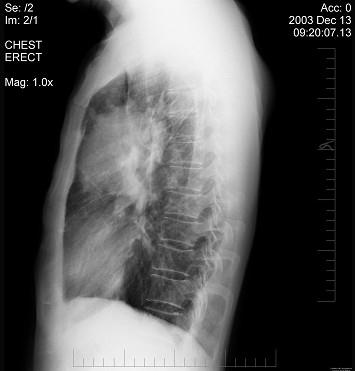

问题 女性,51岁,胸痛数月,痰血2天,X线检查见图,最可能的诊断是 ( )

选项 A.左肺癌 B.左侧炎性假瘤 C.左侧纵隔肿瘤 D.左肺转移瘤 E.支气管扩张

答案 A